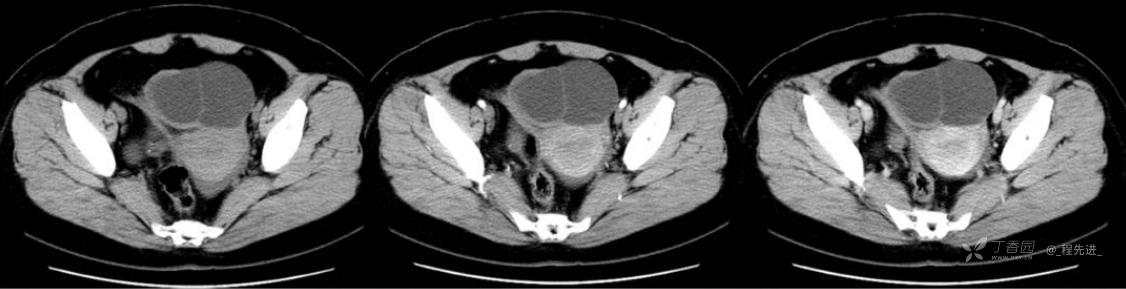

1月特别精彩病例|中老年女性,盆腔包块近半年持续增大【病理已公布】

患者年龄:53岁

简要病史:4年前体检时发现盆腔包块及子宫肌瘤,近半年复查盆腔彩超发现包块持续增大,近1年月经欠规律,伴腰、腹胀。

体格检查:宫颈举痛(+),子宫增大,质地中等,活动可,无压痛;右下腹轻压痛,无反跳痛,左侧附件区未扪及明显包块,无压痛。

阴式彩超:子宫约65*58*44mm大小,子宫肌层可见多个低回声块影,较大的为35*27mm(位于子宫前壁下段偏右侧壁),边界清,内回声欠均匀,后方回声衰减。考虑子宫多发肌瘤。子宫后壁可见一混合回声包块,大小约31*20mm,边界不清,内呈强弱回声,分布不均,考虑子宫腺肌瘤,其他疾患待删。子宫内膜厚6mm,宫颈可见多个囊性暗区,边界清,内透声好,后壁效应增强,较大的为15*11mm。子宫前方偏左侧可探及一大小89*75mm囊性肿块,边界清,壁薄光滑,内透声好,可见分隔光带